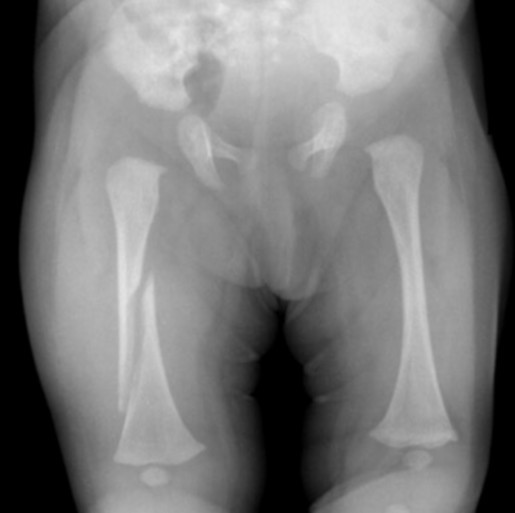

A 6-week-old infant is brought to your clinic with a swollen left thigh. The baby has been irritable for the last two days especially with diaper changes. You obtain the following radiograph.

What is the most likely diagnosis/etiology?

Femur fracture – likely inflicted injury (child abuse) but also consider OIIn addition to appropriate medical therapy, what else needs to be done at this point?

Notify MSW, CPS (DCS), law enforcement -

A 6-week-old infant is brought to your clinic with a swollen left thigh. The baby has been irritable for the last two days especially with diaper changes. You obtain the following radiograph. After gathering a history from the caretakers, there is no known mechanism to explain the injury.

What other radiographic studies are recommended in this context to screen for occult injuries (be specific)?

Skeletal Survey and Head CTIn addition to medical therapy, what else needs to be done at this point?

Notify social work, CPS (DCS), and law enforcement. Call CPS must be included to get credit. -